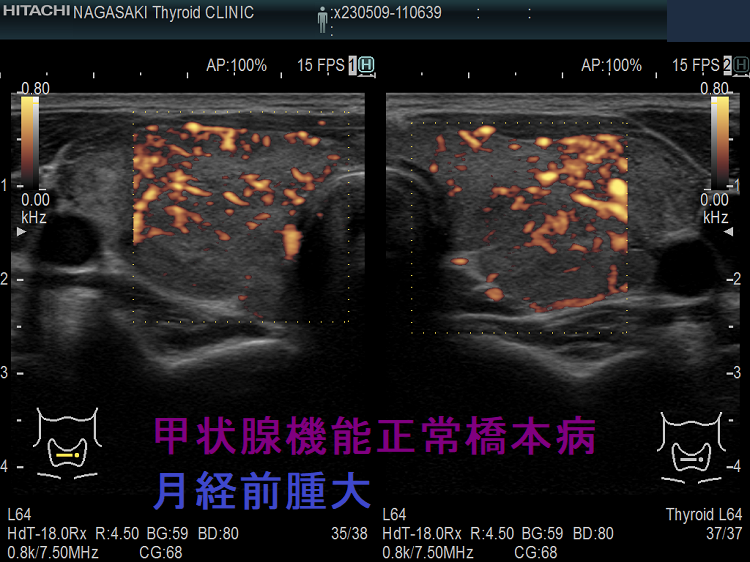

生理前の腫大した甲状腺 単純性甲状腺腫(Simple Goiter) 超音波(エコー)画像。特に、喉(のど)の違和感はありません